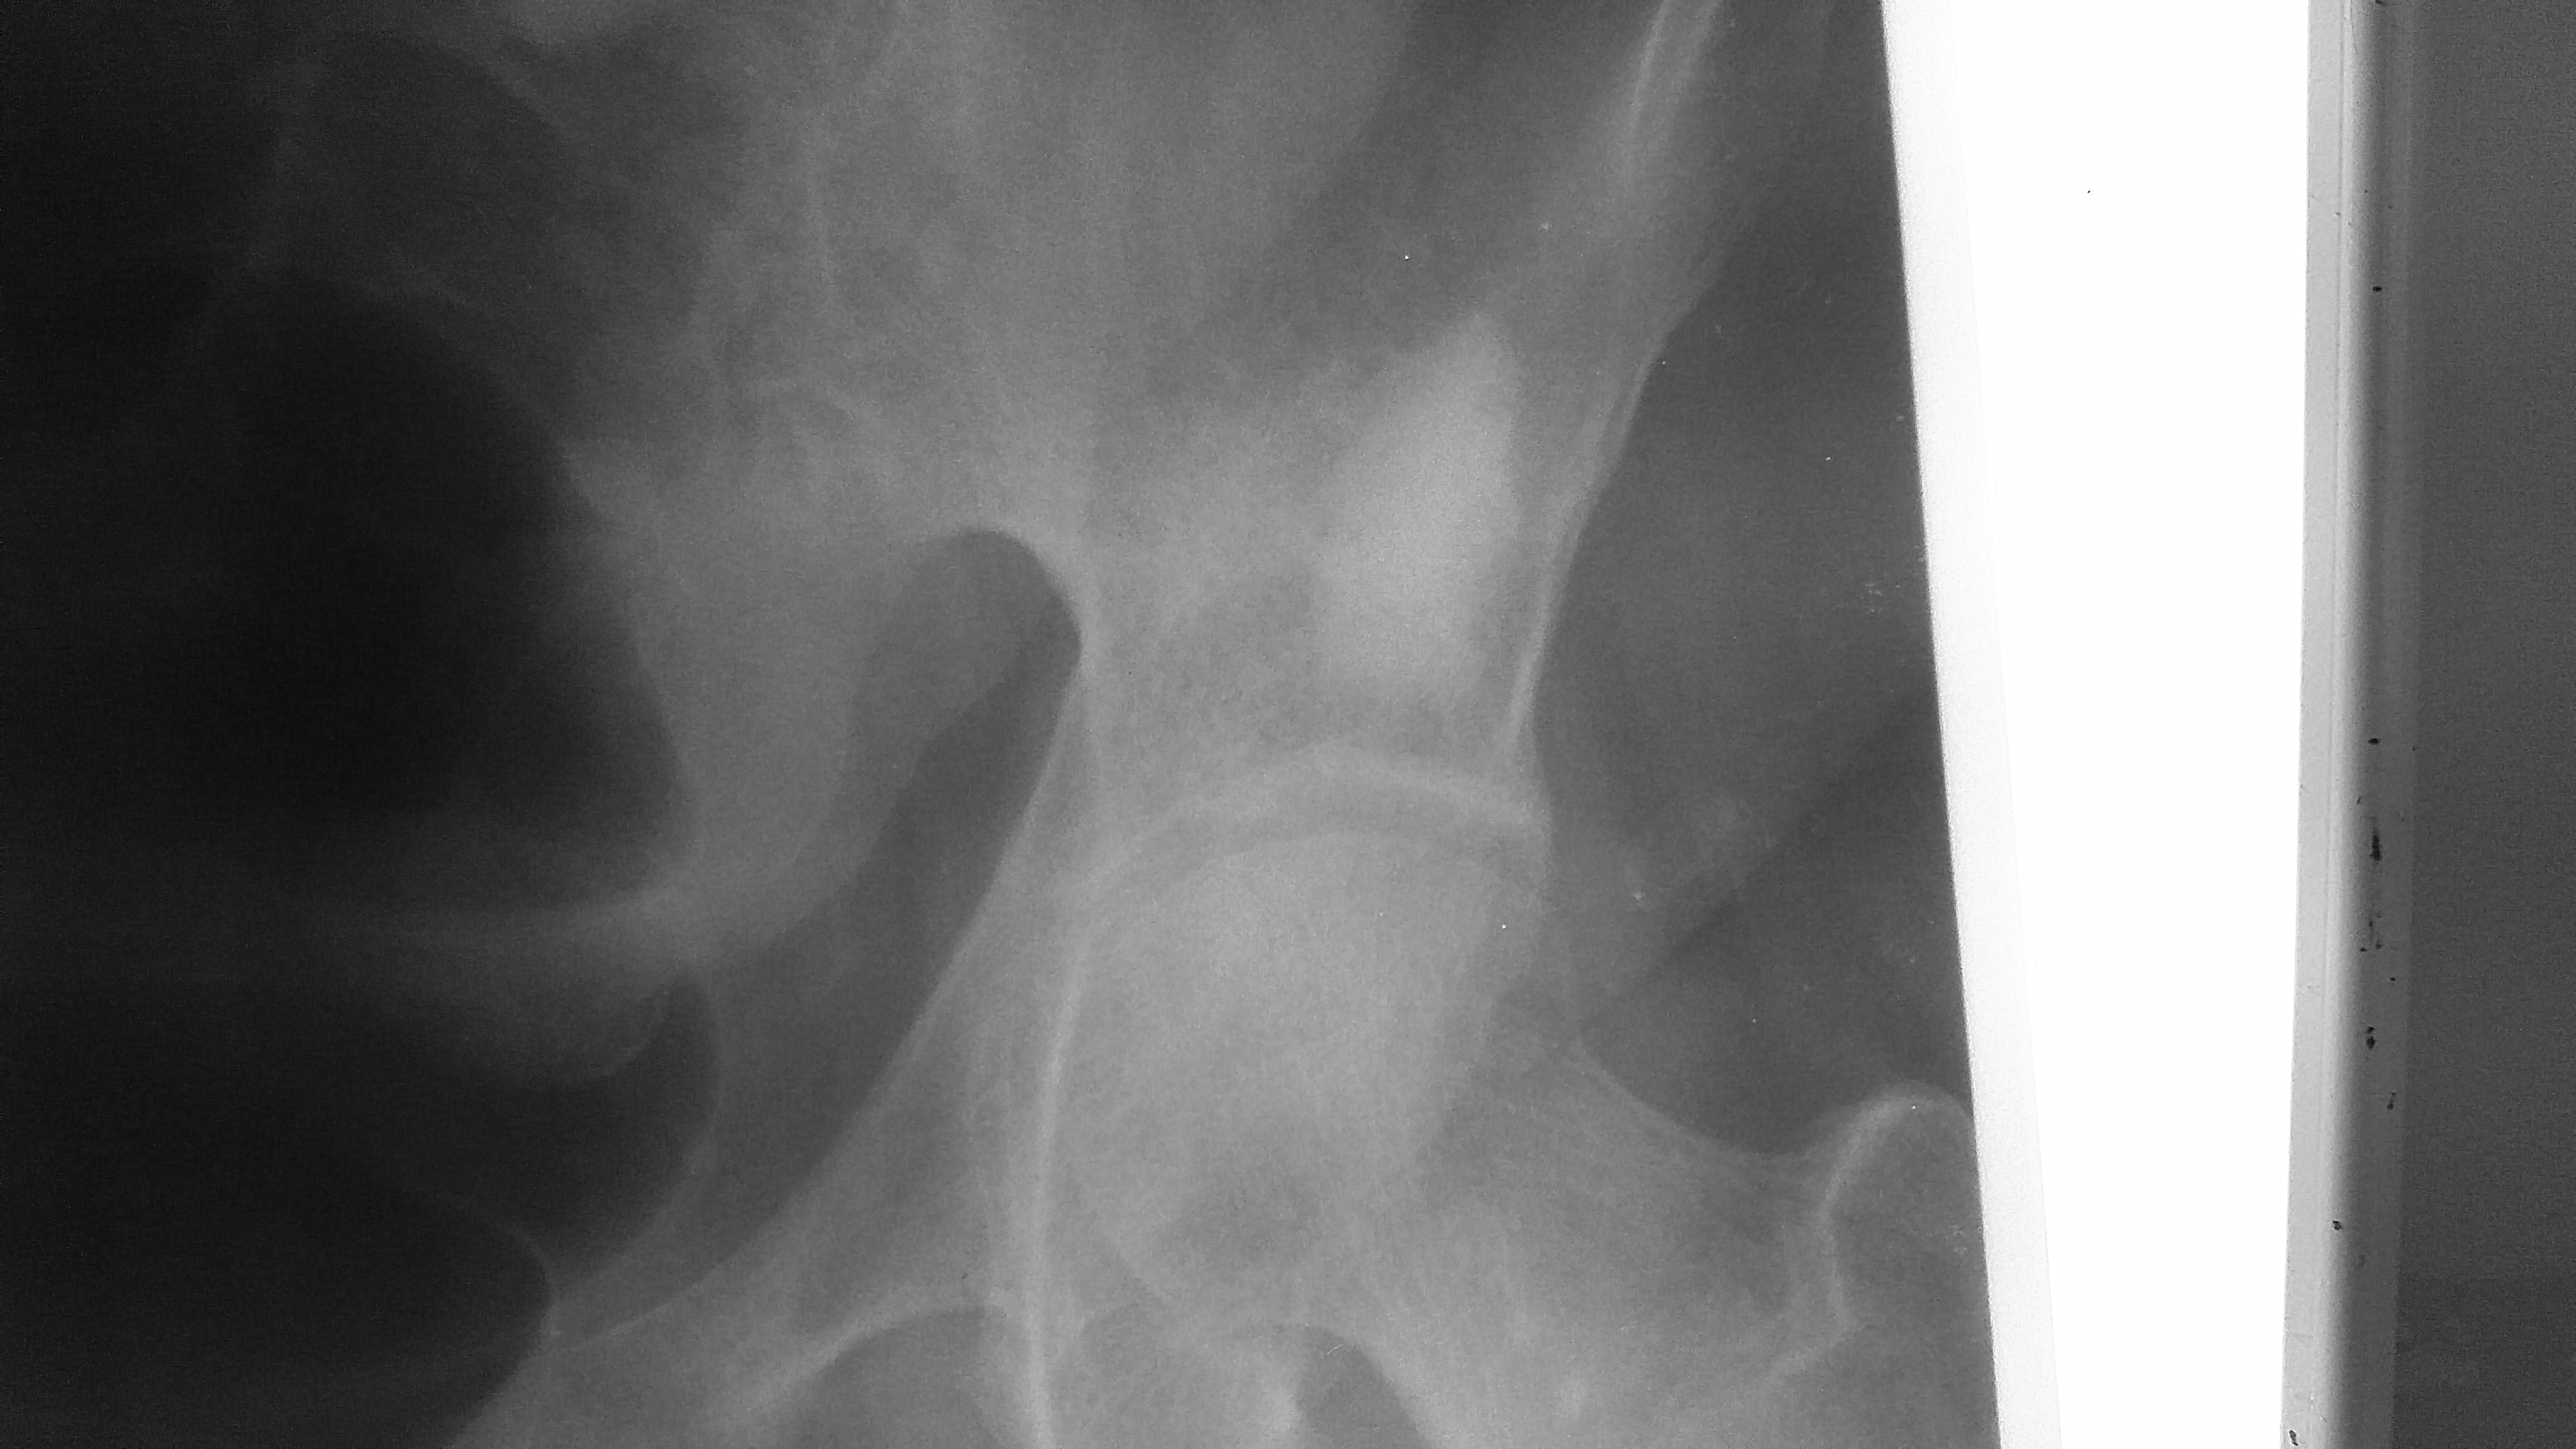

105. Суммация?

Женщина, 1968 года рождения В направлении артроз Смущают участки просветления в седалищной кости и вокруг кость как буд то бы уплотнена. Понимаю, что скорее всего это суммация от мягких тканей 😀...

Тип: Клиническое наблюдение

Область: Скелетно-мышечная система

Модальность: Rg

Дата: 18.12.2021 - 11:24